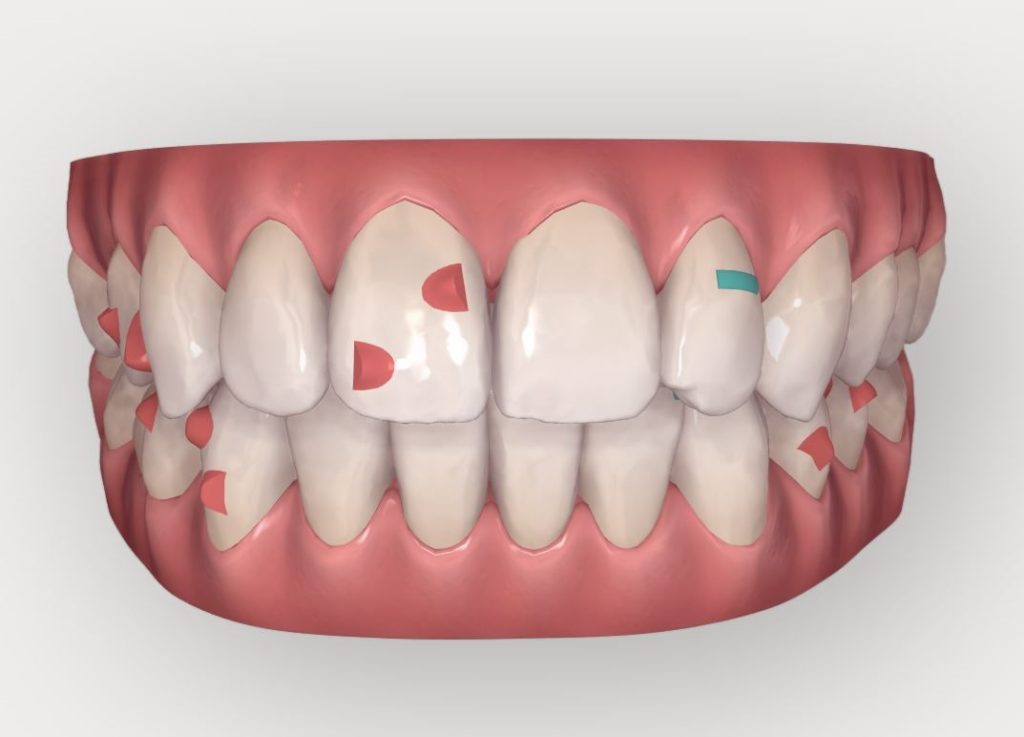

On peut constater ici :

• Une série de 8 aligneurs supplémentaires à changer toutes les semaines cette fois-ci

• Un ajout de 2 RIP au maxillaire pour le décalage des milieux

• Un ajout de 3 RIP à la mandibule pour le décalage des milieux

• Un nombre de taquets très inférieur au premier Clincheck, les mouvements à faire étant bien moins importants au final